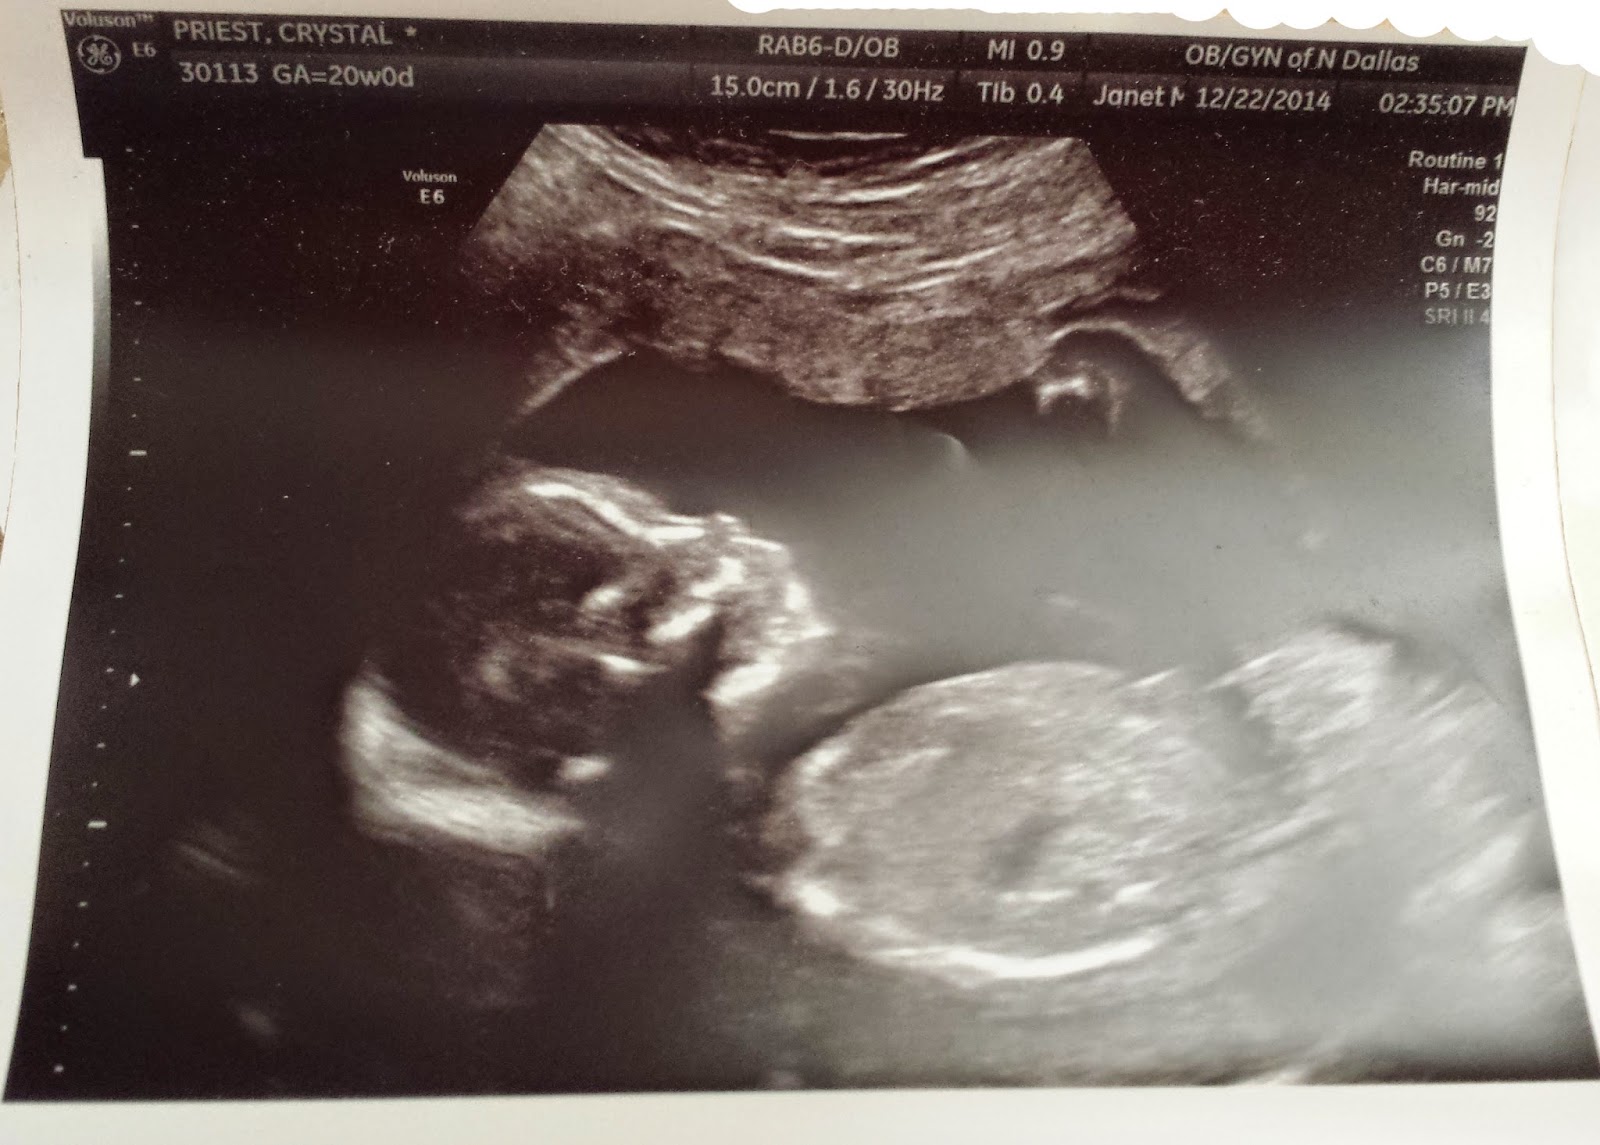

The wait is over! Baby Priest is a GIRL! We are super excited and can't wait to meet Charlotte Lee.

Take a look at the rest of Charlie's 20 week ultrasound shots.